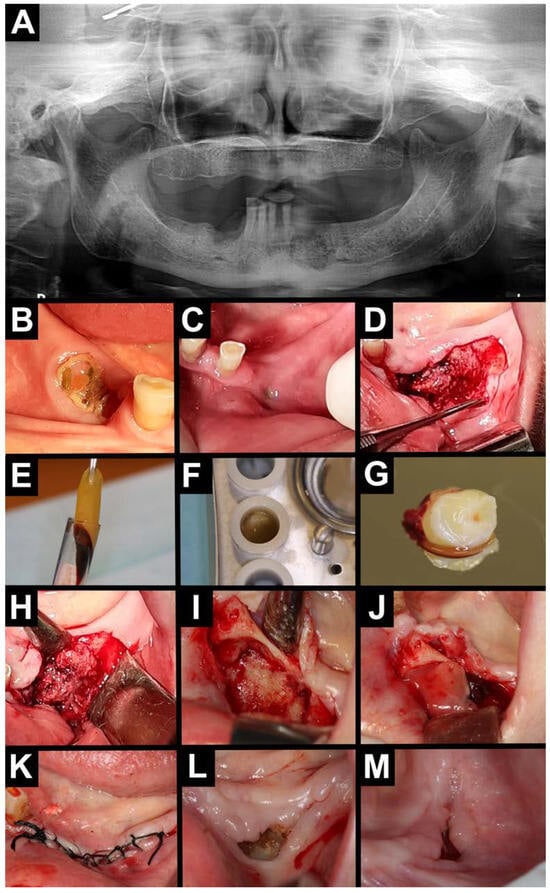

2.3. Surgical Procedure